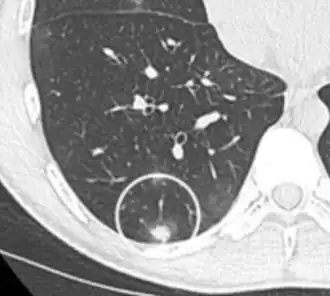

PET-CT of a tuberculoma.

PET-CT of a tuberculoma.